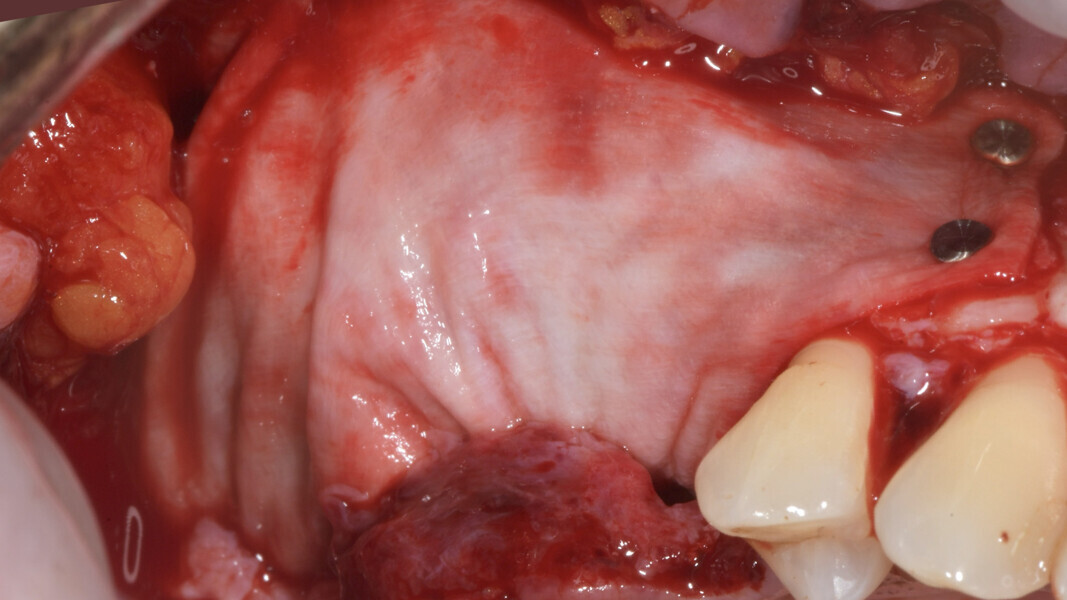

On the day of implant surgery, a para-crestal horizontal incision was made to expose the mesh and remove it, after the removal of the titanium screws and the new bone that had formed over the mesh (Figs. 25a & b, 26). Clinical examination showed complete regeneration of the vertical defect and the absence of pseudo-periosteum or thin pseudo-periosteum (< 1 mm), corresponding to the pseudo-periosteum Type 1 according to the Cucchi classification (Figs. 27 & 28).20